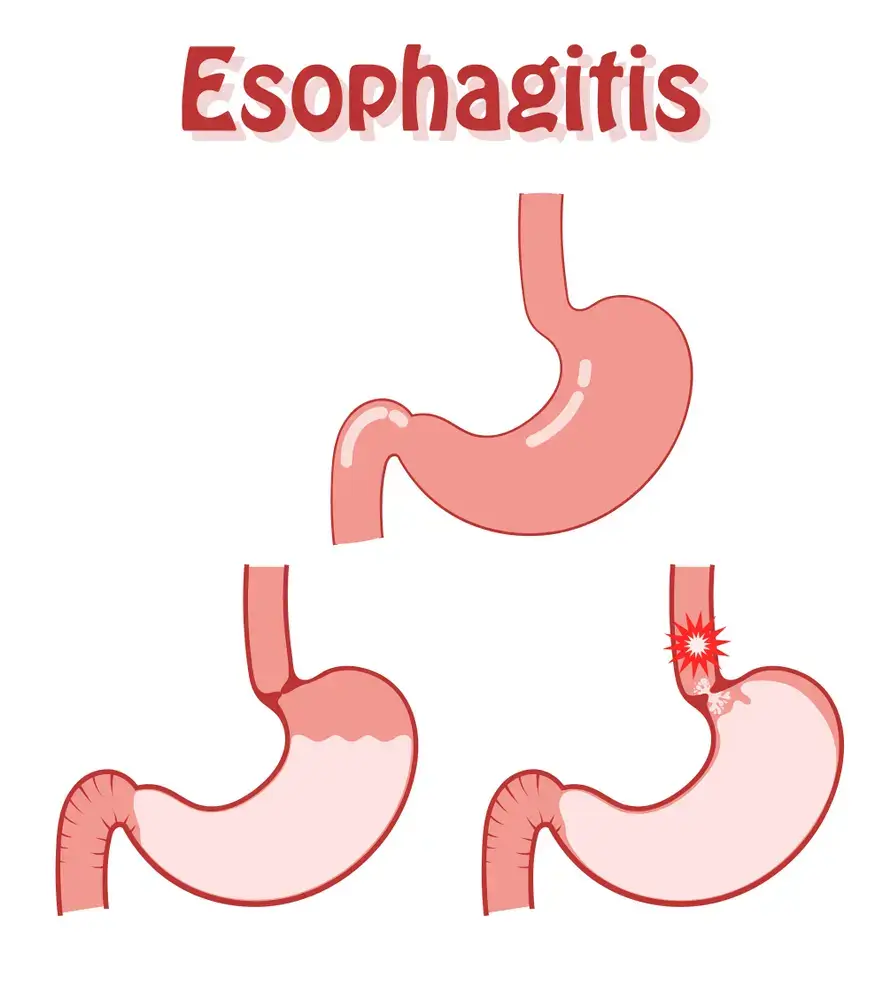

- Esophagitis • Georgetown • Acupuncture • Natural Health Clinic of Halton (March 5, 2022)